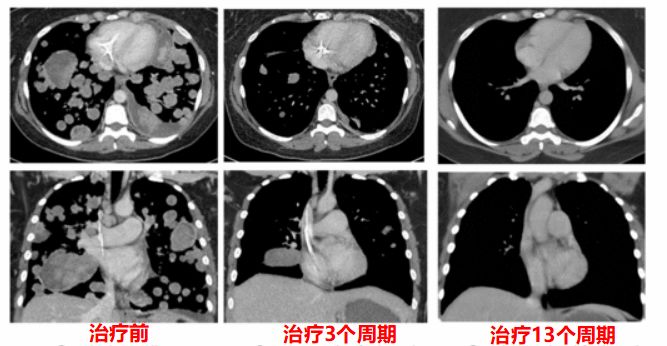

肉瘤患者:接受治疗前,患者的肿瘤细胞已经广泛转移到肺部。开始接受LOXO-101 100mg BID治疗,3个周期后,情况就大为好转,13个周期后,肿瘤几乎完全消失!